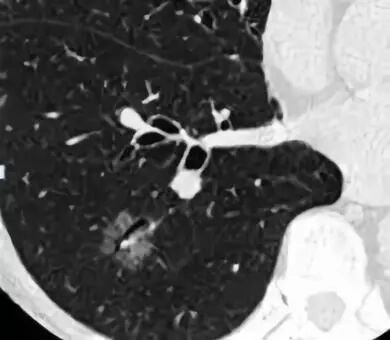

患者的肺像铺路石一样

这是肺内通气灌注不一致的表现,主要是小支气管炎症导致肺内局部积气,像马赛克拼图一样